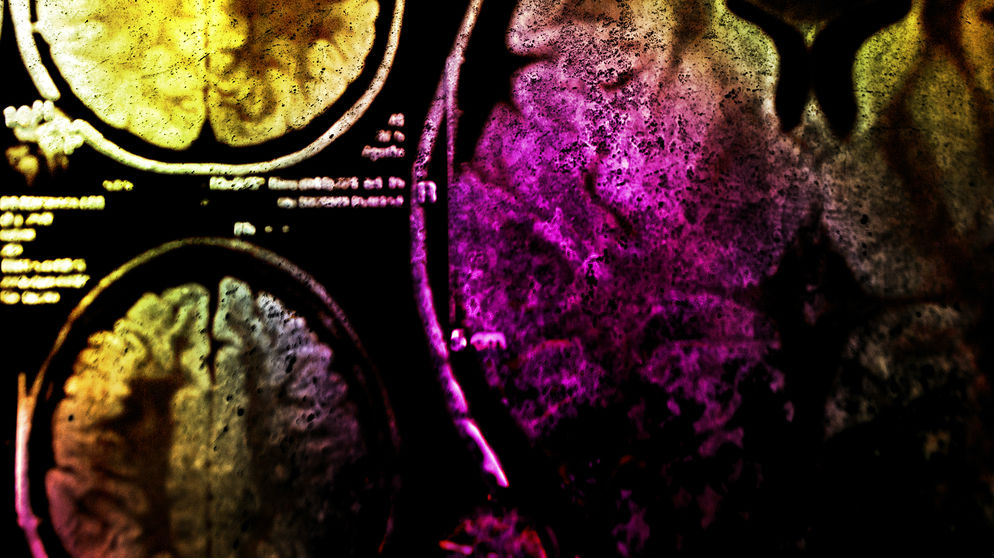

Two months later, in sunny San Diego, I met Komisaruk and Wise at the Society for Neuroscience conference, which gathers approximately 30,000 neuroscientists to discuss the newest advances in the field. They presented the data from my time in the magnet. And they did so with a 3-D movie highlighting the time line of brain activation. (Call it brain porn.) As I watched the film I was struck by the sheer amount of activation.

What happened in my brain during orgasm? Komisaruk and his colleagues saw distinct temporal activity, with different brain areas being recruited as I went from arousal to orgasm and then back around again to rest.

As I roughed up the suspect, so to speak, my genital sensory cortex, motor areas, hypothalamus, thalamus, and substantia nigra lit up. The hypothalamus was no surprise; it has consistently been implicated in all manner of reproductive behaviors, including arousal. The part of the brain that produces oxytocin, is located there too. My motor areas controlled my fingers as I self-stimulated, and my genital sensory cortex registered that stimulation. And the thalamus? It was integrating not only the activity of my wandering fingers but also the memories and fantasies I used to help build up my arousal. The substantia nigra, an area rich in dopamine-producing neurons, paired with the PVN’s oxytocin release, had me feeling nice and relaxed.

Areas implicated in memory, integration of sensory information, and emotion also became active. As my orgasm came to a close, the hypothalamus turned back on, and reward areas like the nucleus accumbens and caudate nucleus were flooded with dopamine. That was what gave me that final rush. Getting to that point involves a variety of cognitive, emotional, and sensory components—even when it’s just you doing the work.